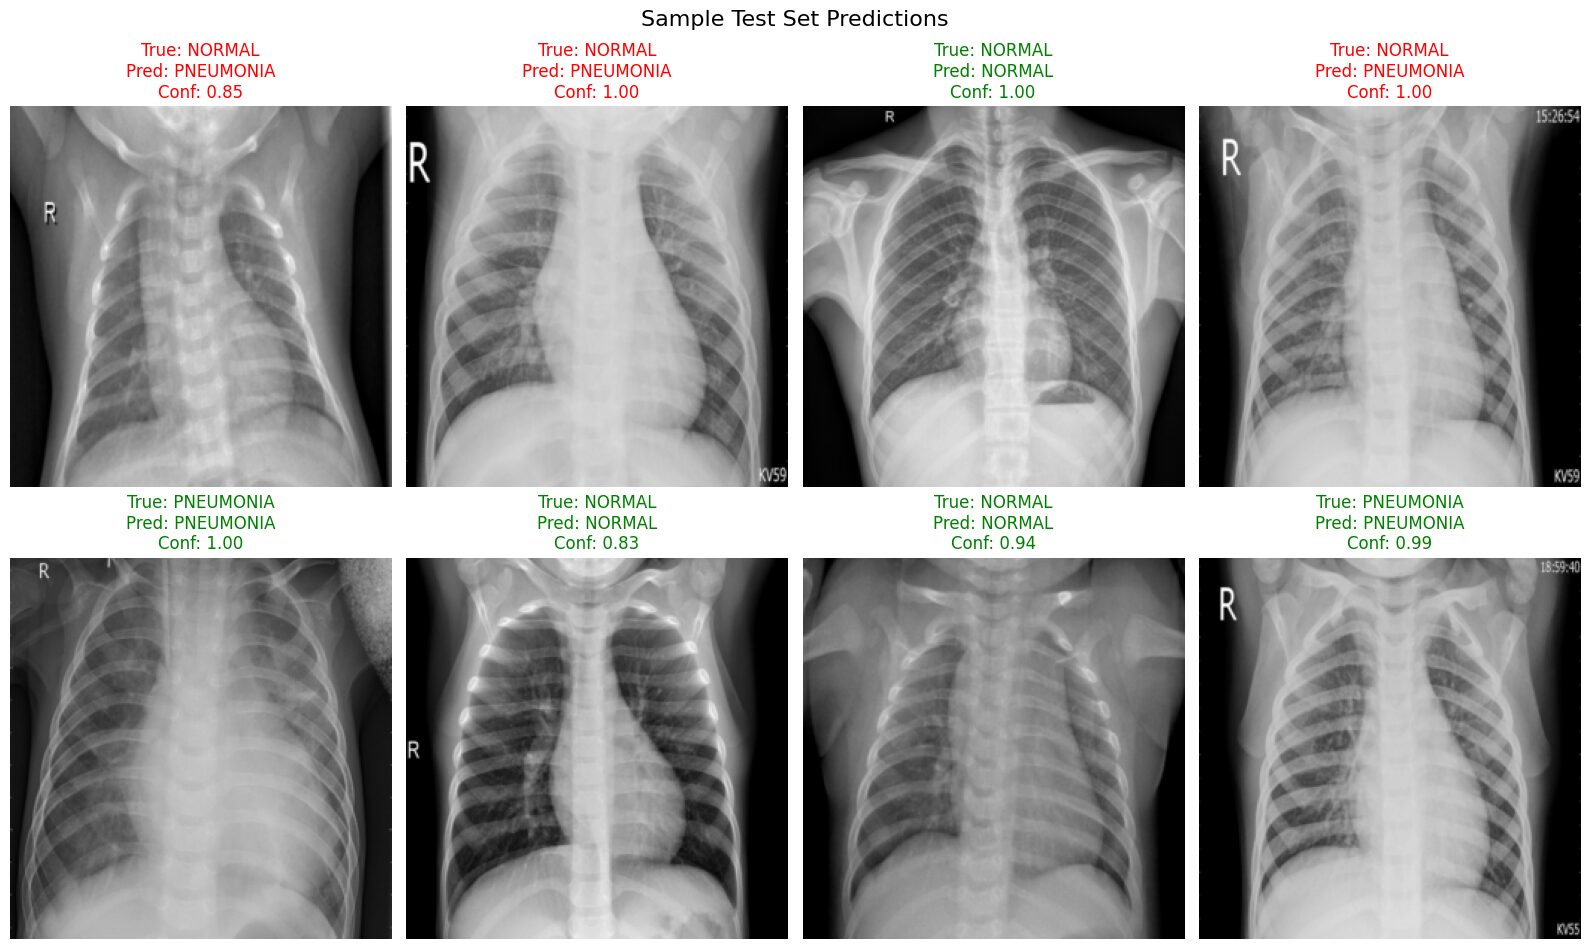

This visualization provides concrete examples of the model's behavior on the test set:

- We can clearly see examples of both correct (green titles) and incorrect (red titles) predictions made by the model.

- It allows us to observe the model's confidence for each prediction. Notice in this batch that the confidence scores are generally quite high (often >0.80), even for some of the incorrect classifications.

- Most importantly, we can identify potential patterns in the errors. In this specific sample batch, the errors primarily consist of

True: NORMALimages being incorrectly classified asPNEUMONIA, sometimes with high confidence. This visually reinforces the low Specificity (low Recall for the NORMAL class) identified in our quantitative evaluation metrics and highlights the model's tendency to misclassify normal cases.